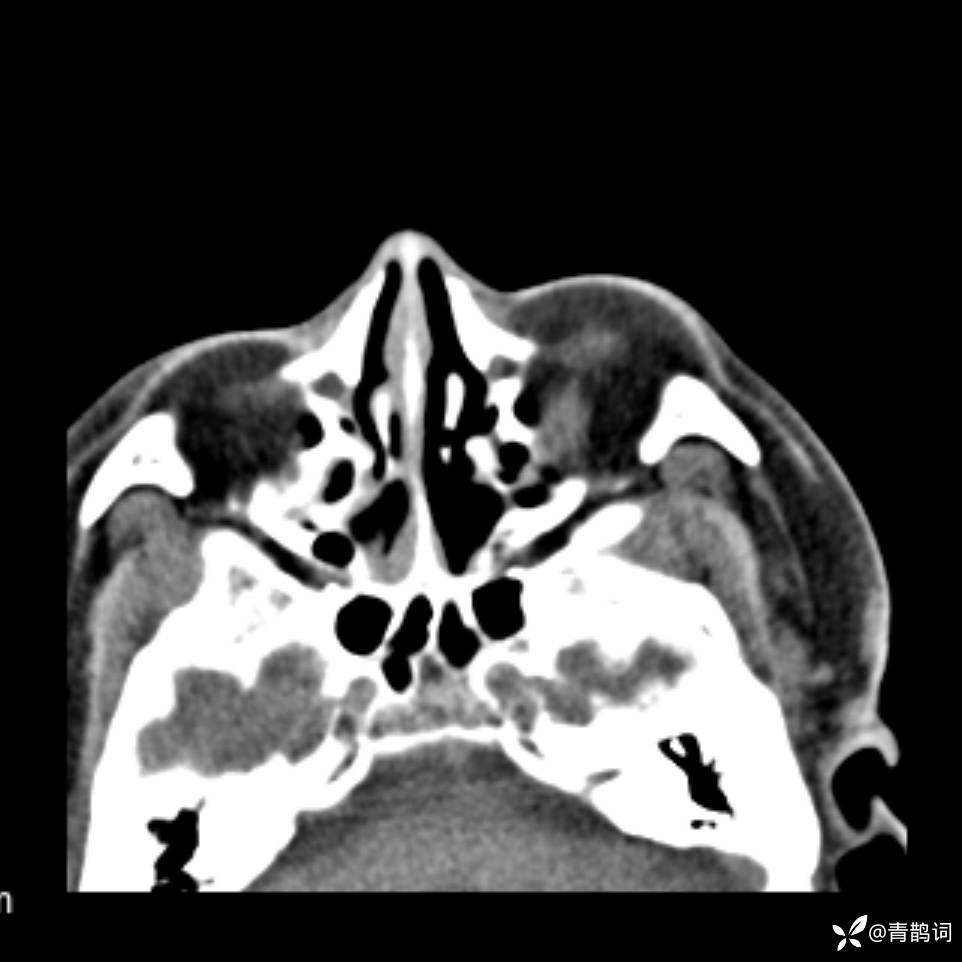

患者年龄:30岁。

患者性别:男。

简要病史:左颜面部肿胀2年,反复咳嗽咳痰,逐渐加重。

结合病史及影像学表现,期待评论区各位老师各抒己见~